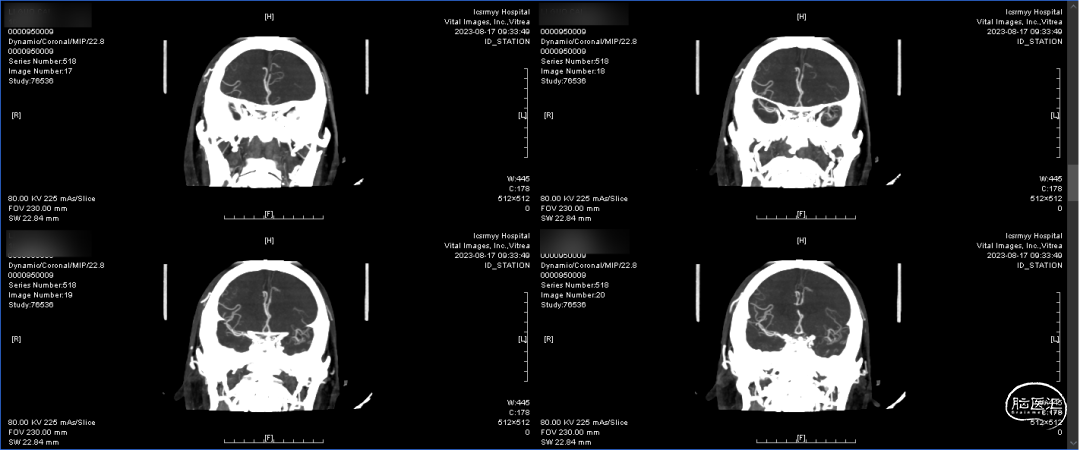

术前CTA:双侧颈内动脉闭塞,代偿可。

术前CTA:颅内代偿可。

左颈总正侧位:左侧颈内动脉闭塞,可见血管残端。